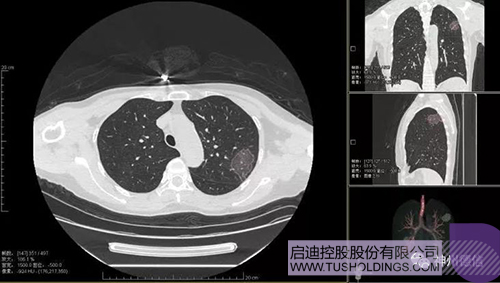

神州德信新冠肺炎检测及智能量化分析系统

Bsports·必一体育(中国)官方网站战略投资企业神州德信作为国内领先的肺部影像人工智能企业,针对新型冠状病毒肺炎开发了智能检测及量化分析系统,并在陕西、重庆等地定点医院投入使用。该系统在疑似病例大规模快速筛查及精准诊断方面发挥了重要作用,特别是其具有的肺炎患者临床影像跟踪量化随访功能,为快速有效阻断疫情扩散提供了有力武器。